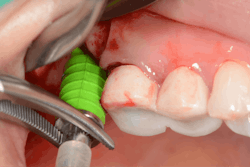

Hydraulic sinus lifting is a technological leap forward in sinus lift procedures. These innovative devices utilize hydraulic pressure to lift the sinus membrane gently and precisely, creating sufficient space for implant placement without the need for excessive bone manipulation (figure 3).

Hydraulic lifts can effectively prevent many of the aforementioned complications. Membrane perforations and injury to nearby vital structures are minimized because of the use of millimeter-precise drill stoppers, as well as simply using saline instead of blunt instruments to separate the thin sinus membrane. The flat-ended drills and stoppers in hydraulic techniques eliminate much of the guesswork involved in drilling to breach the sinus.

There is no manual bone manipulation, meaning hydraulics are less invasive and therefore promote faster healing for patients. Because mallets are not used, the patient experiences less trauma and doesn’t suffer related side effects such as tinnitus or concussions. Most importantly, unlike traditional methods that involve manual force, hydraulic lifts offer controlled and predictable elevation of the sinus floor, minimizing trauma to surrounding tissues and reducing postoperative complications.